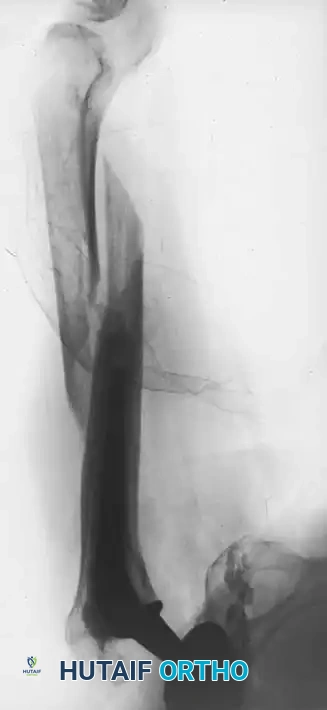

Associated Surgical & Radiographic Imaging